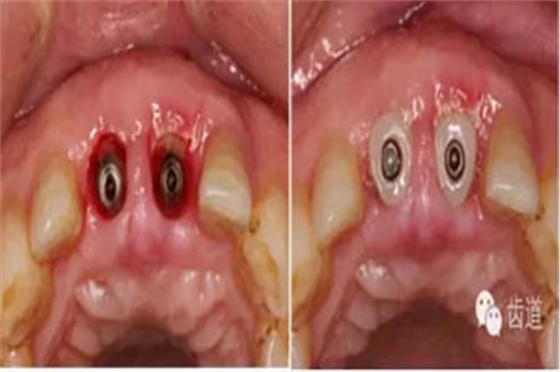

更換大直徑愈合基臺(tái)

換用個(gè)性化愈合基臺(tái)(術(shù)后一周)

半年后復(fù)診(牙齦袖口)

戴牙(基臺(tái)就位)